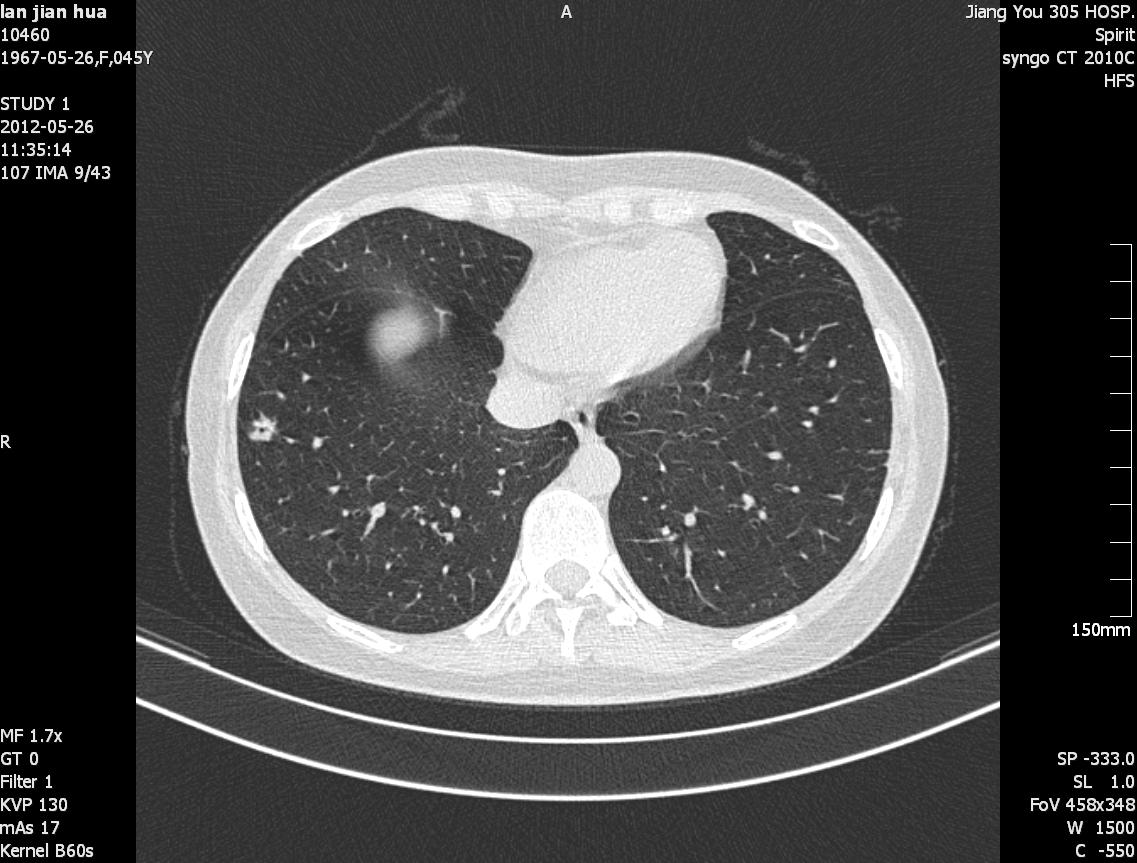

ct38787:女性,45y,肺部结节(近期出结果)